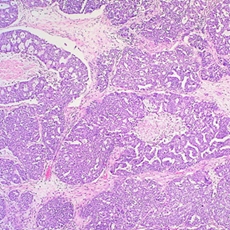

The method uses a statistical calculation to interpret changing levels in women's blood of a protein called CA125, which is linked to ovarian cancer. This gives a more accurate prediction of a woman's individual risk of developing cancer, compared to the conventional screening method which uses a fixed 'cut-off' point for CA125. The new method detected cancer in 86% of women with invasive epithelial ovarian cancer (iEOC), whereas the conventional test used in previous trials or in clinical practice would have identified fewer than half of these women (41% or 48% respectively).